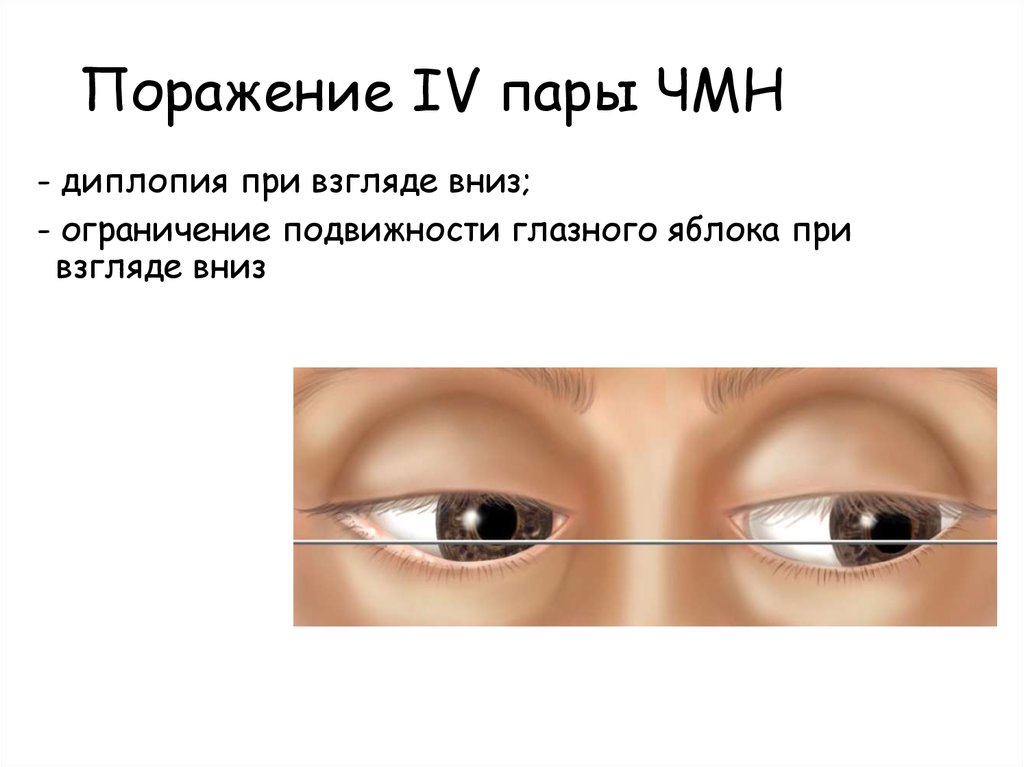

Диплопия: механизм развития и методы лечения